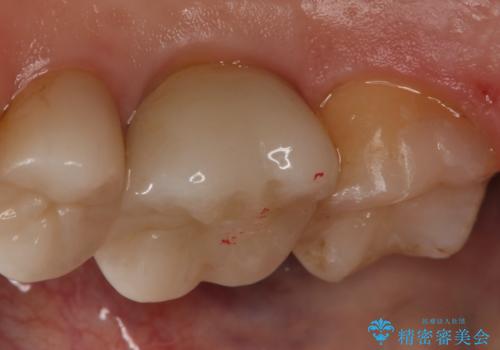

- 右上7番の銀歯のやりかえを主訴に来院された患者様です。

切削量・形態を考慮し、セラミックインレーでの治療を計画しました。